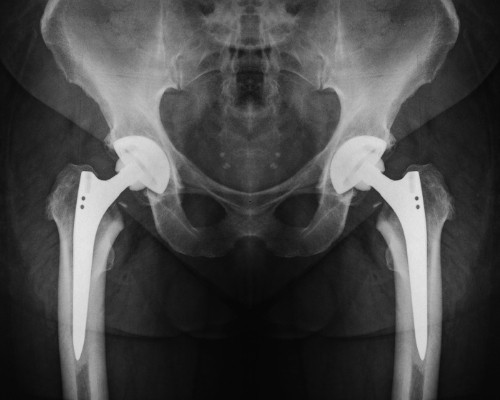

Total Hip Replacement

When hip arthritis becomes severe enough that walking, sleeping, or standing feels unbearable, it may be time for a permanent fix. Dr. Mehta, an expert hip surgeon in San Jose, offers total hip replacement using durable implants and precise techniques to restore smooth movement and get you back to living pain-free.